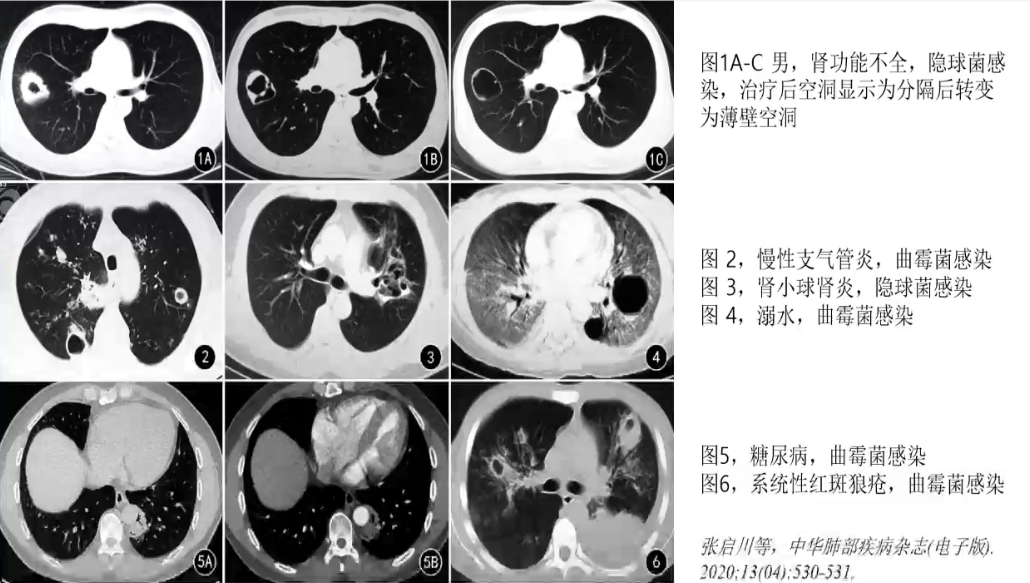

空洞(cavity)

真菌感染空洞形成机制

❖ 细胞免疫受损或完全丧失者

√真菌直接造成肺结构破坏,周围产生轻度炎症反应

❖ 非免疫抑制者

√结节或实变内坏死物及真菌孢子被单核细胞、巨噬细胞和中性粒细胞吞噬并逐渐被吸收形成,多见于感染恢复期